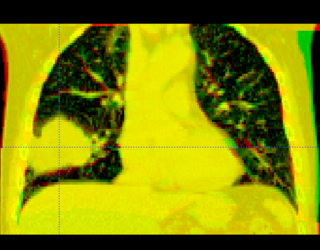

Here is another example, showing the magnitude of tumor regression that can occur during treatment. (Sorry, low resolution image).

Thorax is a special case. Patient images are acquired using 4D-CT, and radiation treatment plan can be evaluated at each breathing phase. The volumes are aligned using deformable registration, and radiation dose from each phase is accumulated into a reference phase (e.g. exhale). This process is called "4D treatment planning."